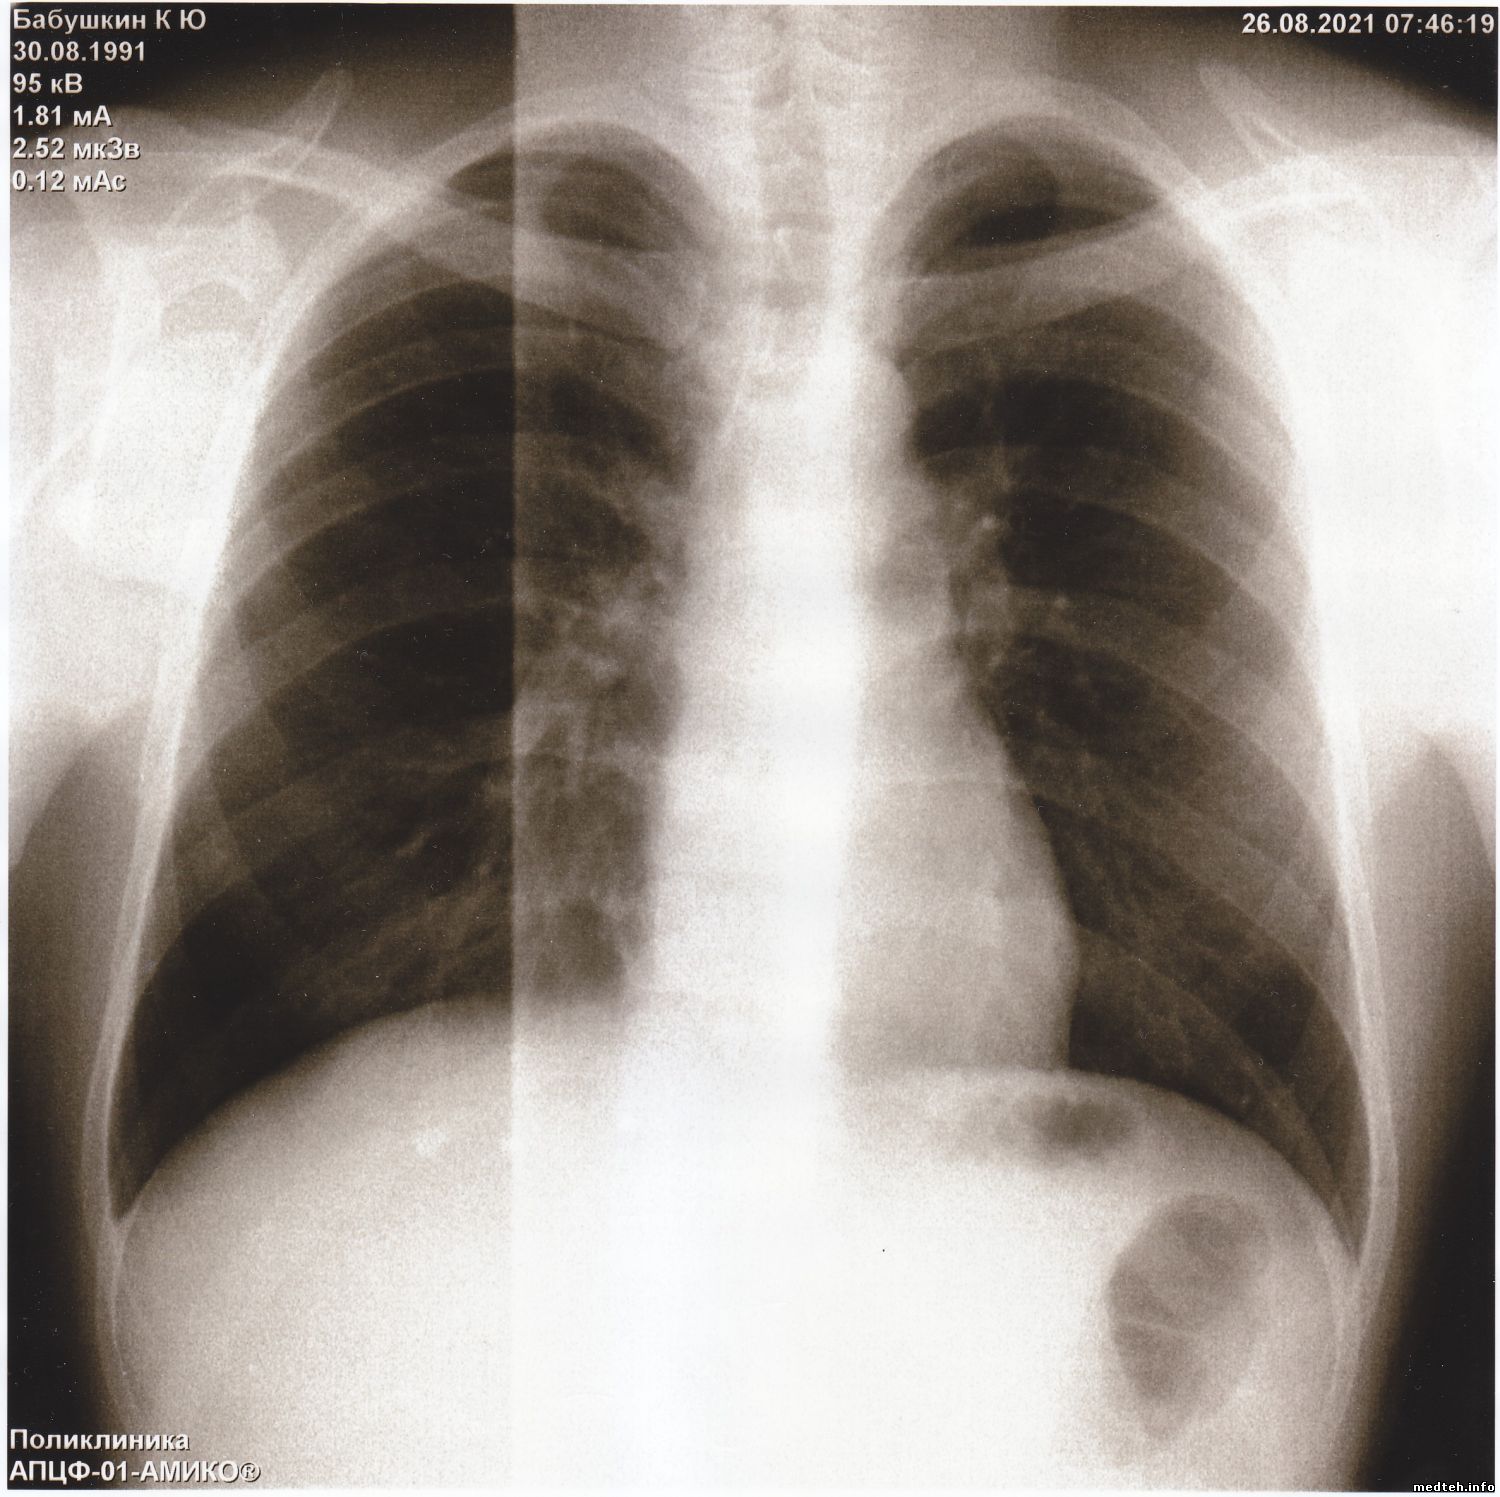

Здравствуйте коллеги.

Прислали снимки из другого города, просят помочь устранить неисправность.

Аппарат я не видел. По снимкам, конечно, не установишь причину, может у кого была такая проблема.

Появились горизонтальные и вертикальные полосы на снимках, делает снимки - смещённые на половину. Снимок есть, видны легкие и все остальное, но полосы очень мешают докторам.

Подскажите что можно сделать в данной ситуации.

Друзья, думаю, вы знаете решение этой проблемы.

Фото прилагается.

Всё решилось просто - тренировка - калибровка и нормальные снимки.